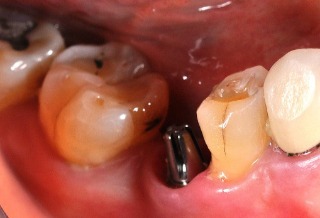

植牙前

植牙全瓷牙冠

植牙後

更多植牙案例